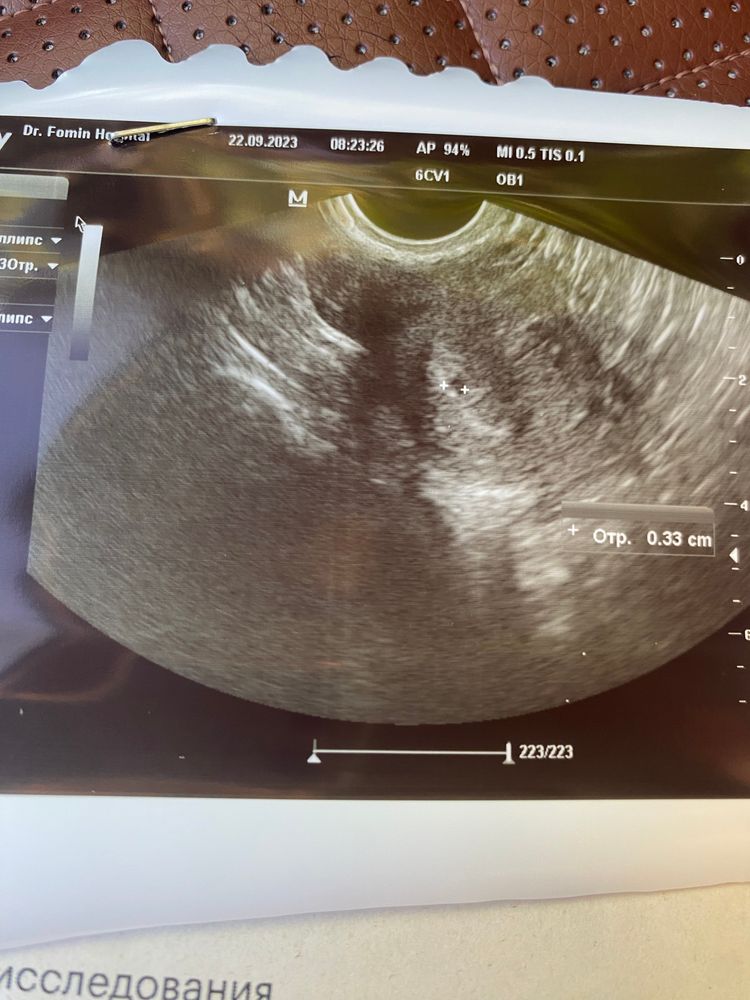

Узи 22 дпп

Анализы и процедуры. Помощь в расшифровке результатовДевочки, сегодня была на узи. 22дпп

на узи увидели толк о ПЯ 3,3 хгч на 21 дпп сдавала был 1827

мне не понятно на узи, в плодном яйце что-то белое, кто разбирается посмотрите пожалуйста… есть ли вообще шансы у нас? По идее на этом сроке долже быть эмбрион уже и желточный мешочек….. да и хгч долже быть больше